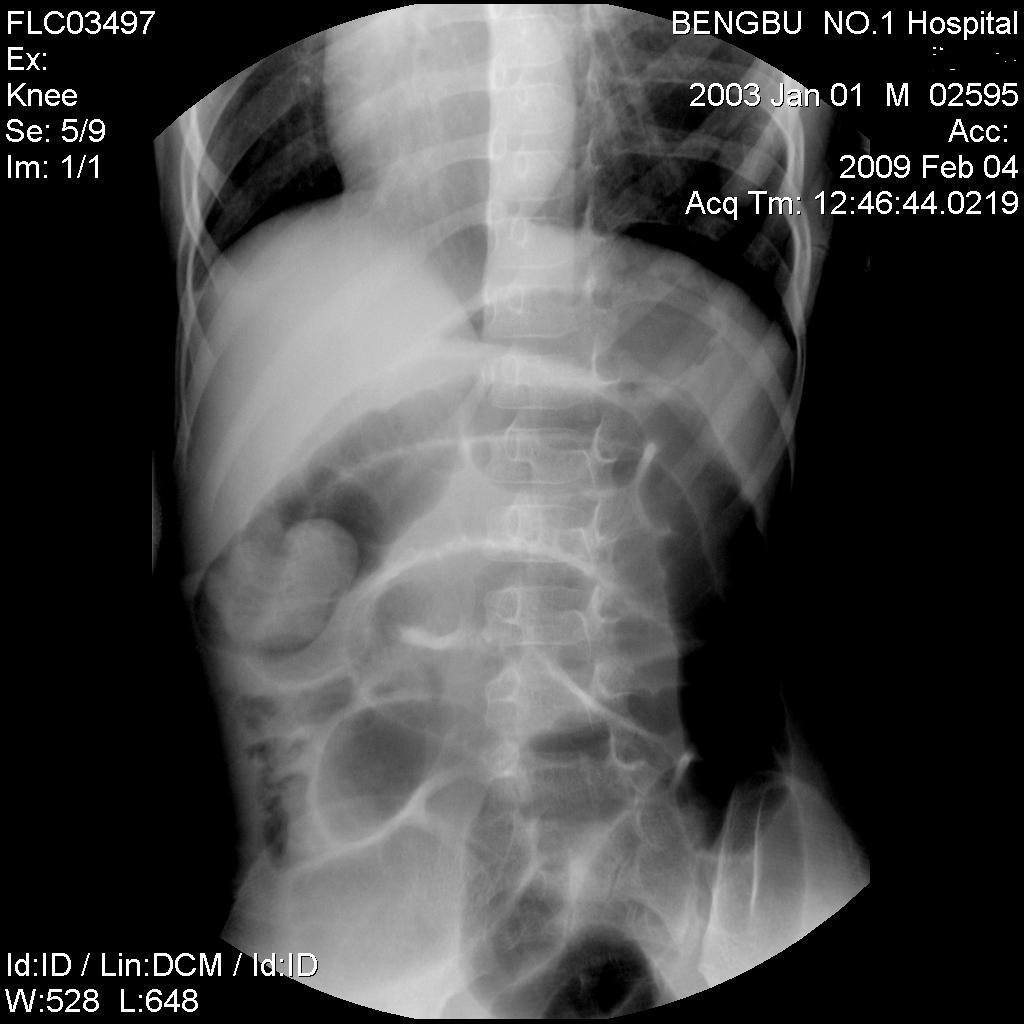

以下是引用杀毒软件在2009-2-5 14:51:00的发言:[br]提示肠梗阻----原因待查----大跨度肠绊---绞窄性可能性小---首选考虑---肠套叠或功能 性肠梗阻可能

以下是引用余辉在2009-2-5 8:52:00的发言:[br]考虑绞窄性肠梗阻,建议行钡剂灌肠检查

以下是引用随光逐影在2009-2-5 1:00:00的发言:[br]考虑肠套叠;建议行钡剂灌肠检查。